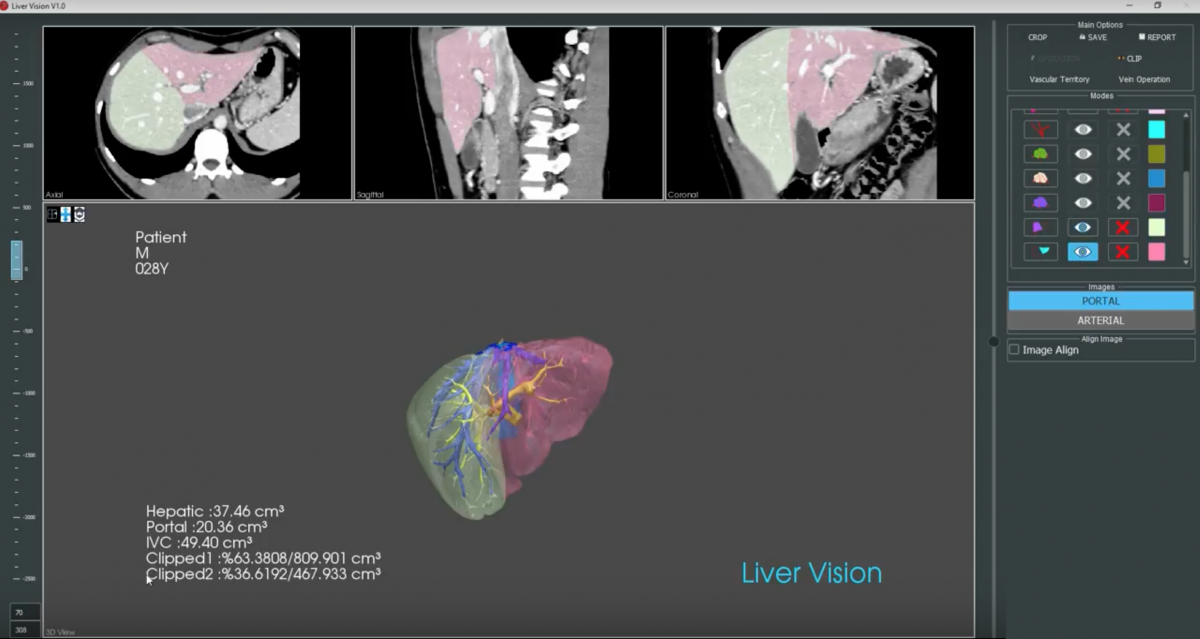

The aim of this study is to assess the accuracy and functionality of a new semi-automated liver volumetry software (LiverVision® software) in predicting the clean future liver volume in patients undergoing liver surgery.

Stage 1 - Validation

Prospective validation of the new semi-automated volumetry software (LiverVision®) will be conducted in living liver donors undergoing partial hepatectomy. The reference standard will be the true weight of the donor grafts immediately after resection and prior to transplantation. The volumetric measurements of the new semi-automated software will be compared with those of existing, established manual measurements typically performed by radiologists and liver surgeons (PACS). The interclass correlation coefficient among the different software as well as among radiologists and surgeons will be further assessed.

The index test will be the new semi-automated liver volumetry software measurements for both study stages mentioned above.